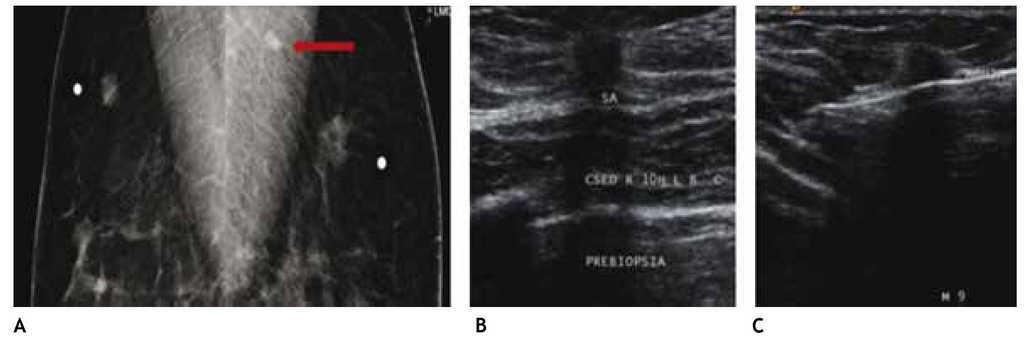

Otra de las ventajas del sistema digital son la rapidez en la adquisición con almacenamiento de la imagen, cada componente puede ser optimizado y/o manipulado para hacer más evidentes los hallazgos de una lesión sospechosa, y también ofrece la posibilidad de aplicaciones avanzadas no existentes en el sistema analógico, como la telemedicina, sustracción por energía dual, mastografía contrastada, biopsia digital y tomosíntesis (mastografía tridimensional), ésta última ya aceptada por la FDA a partir de enero del 2011, la cual consiste en una serie de imágenes tridimensionales, adquiridas en diferentes ángulos de la glándula mamaria, con baja dosis de radiación ionizante, lo cual elimina sobreposición de estructuras, y permite mejor valoración de los márgenes de una lesión (figs. 1A y B), reduce el número de proyecciones adicionales y por lo tanto, de compresiones mamarias así como de falsas positivas. Esta nueva tecnología es de gran utilidad en mama densa, asimetrías y distorsiones de la arquitectura6.

Figura 1A) Mastografía digital: tumoración de contornos microlobulados en CSI. B) Tomosíntesis, se aprecian contornos espiculados con mayor claridad (flecha), BIRADS 5: cáncer ductal infiltrante.